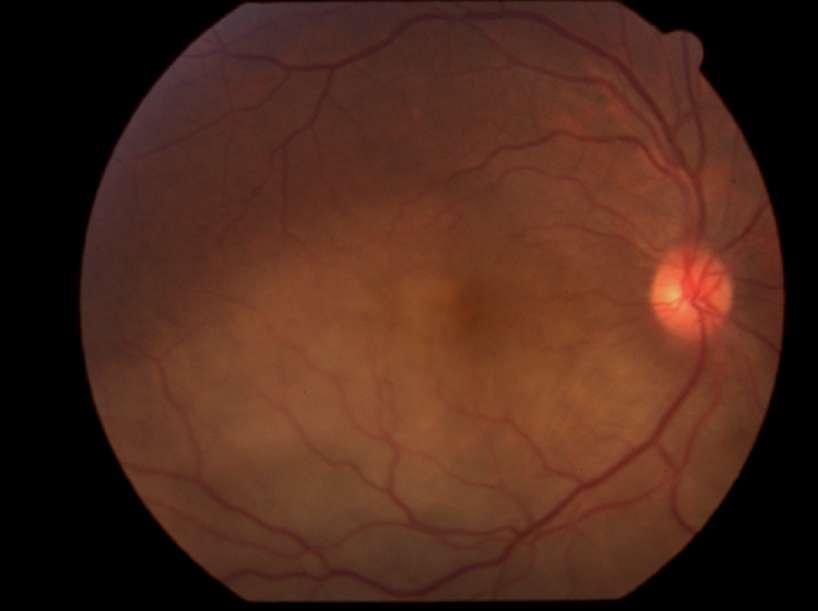

Caso aportado por Dra. María José Vergara

Aü Fondo de ojo OD (Imagen A, B y C): Lesión pigmentada localizada a nasal a nivel coroideo, cuyas mediciones son de aprox 10x4mm en sus ejes cefalocaudaltransversal respectivamente

ü Mujer 70 años refiere cuadro de 1 mes de evolución caracterizado por fotopsias y entopsias en ojo derecho con AV conservada.

B C